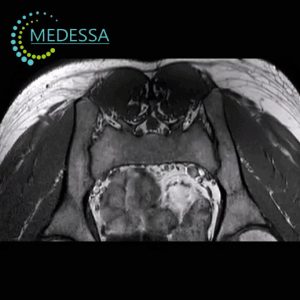

Spine MRI

Magnetic Resonance Imaging (MRI) is the gold standard for diagnosing spine conditions due to its non-invasive and highly informative nature. This method is completely safe and does not use radiation, offering an advantage over X-rays and CT scans. MRI allows detailed evaluation of intervertebral discs, ligaments, muscles, nerve roots, blood vessels, spinal cord membranes, and other structures.

MRI helps detect the following conditions:

• Benign and malignant spine tumors;

• Metastases of malignant tumors, their size and precise location;

• Multiple sclerosis;

• Inflammatory processes in the spinal cord;

• Osteochondrosis;

• Protrusions and herniated discs;

• Spinal joint deformities;

• Congenital and acquired spinal deformities.